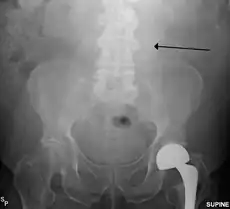

The faint outline of the calcified wall of an AAA as seen on plain X-ray -